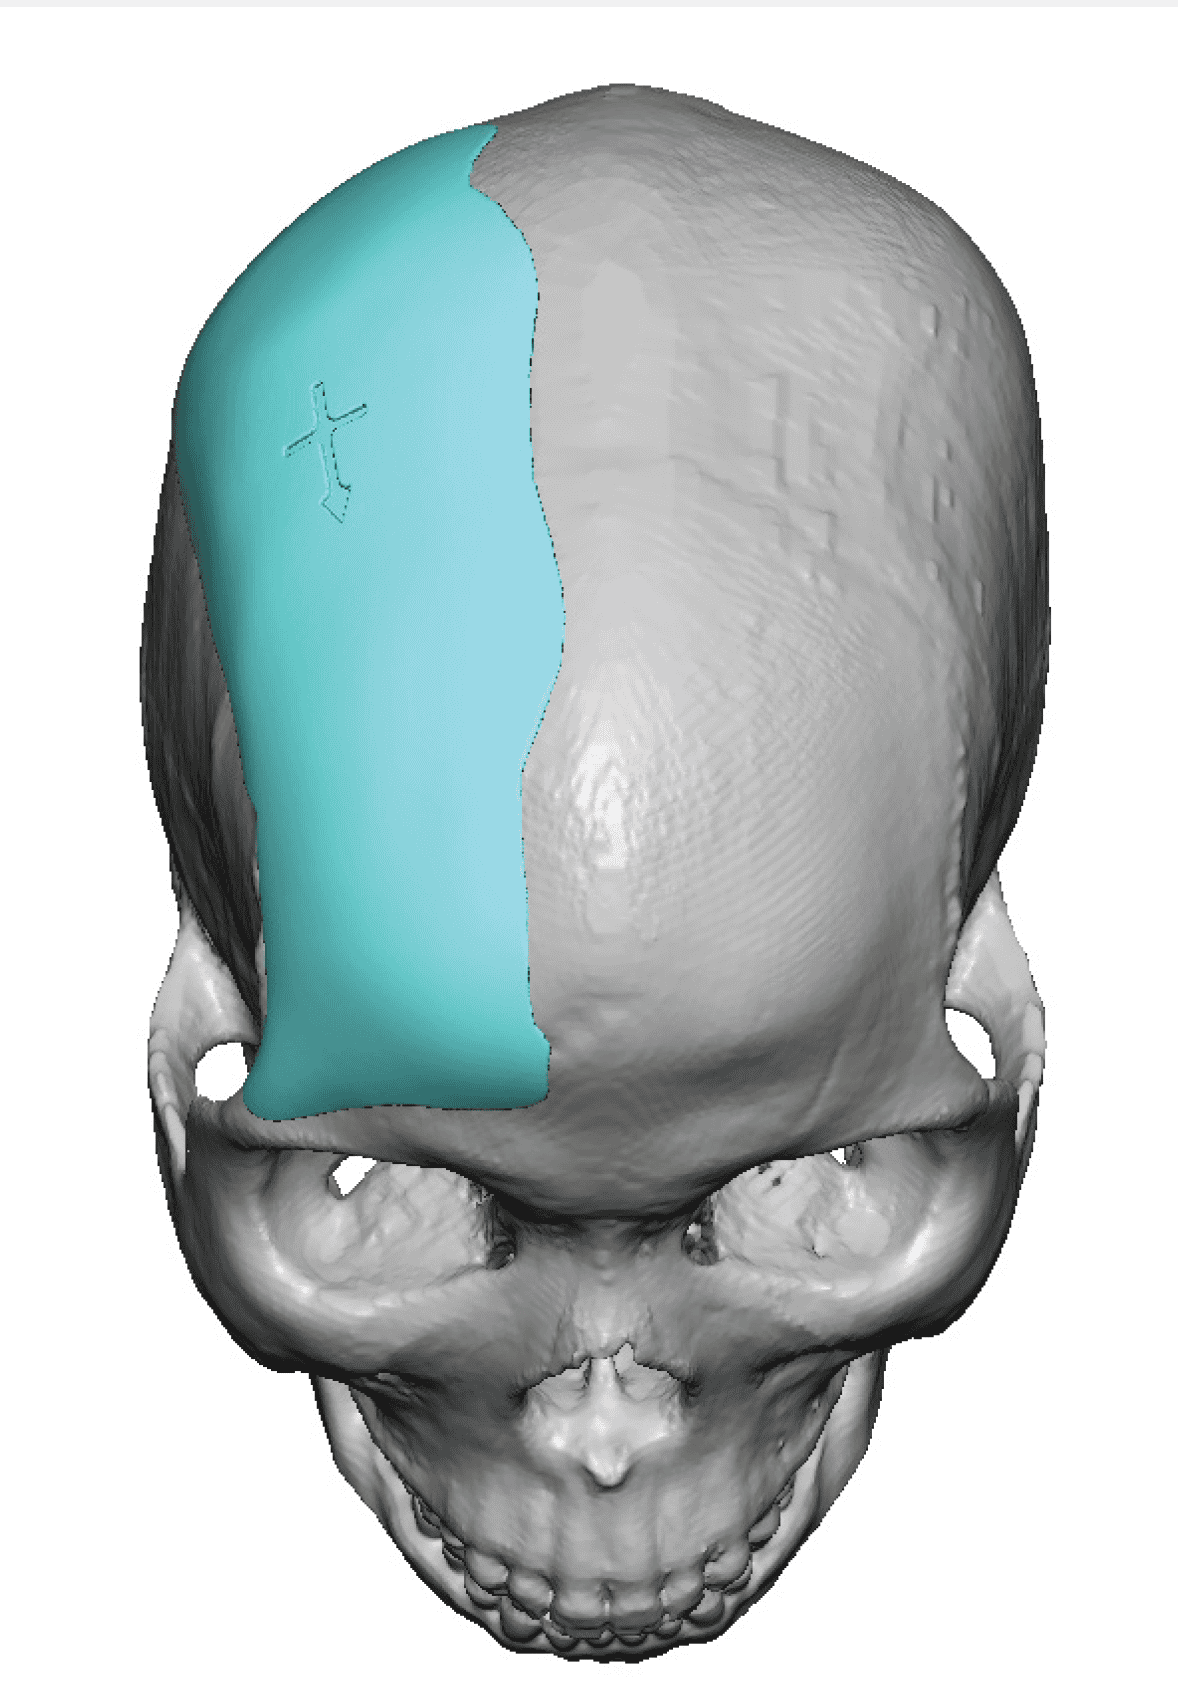

Reconstruction of loss of frontotemporal craniotomy bone flap from neurosurgery.

Reconstruction of full-thickness skull defect with computer-generated HTR-PMI cranial implant.

Reconstruction of loss of frontotemporal craniotomy bone flap from neurosurgery.

Reconstruction of full-thickness skull defect with computer-generated HTR-PMI cranial implant.